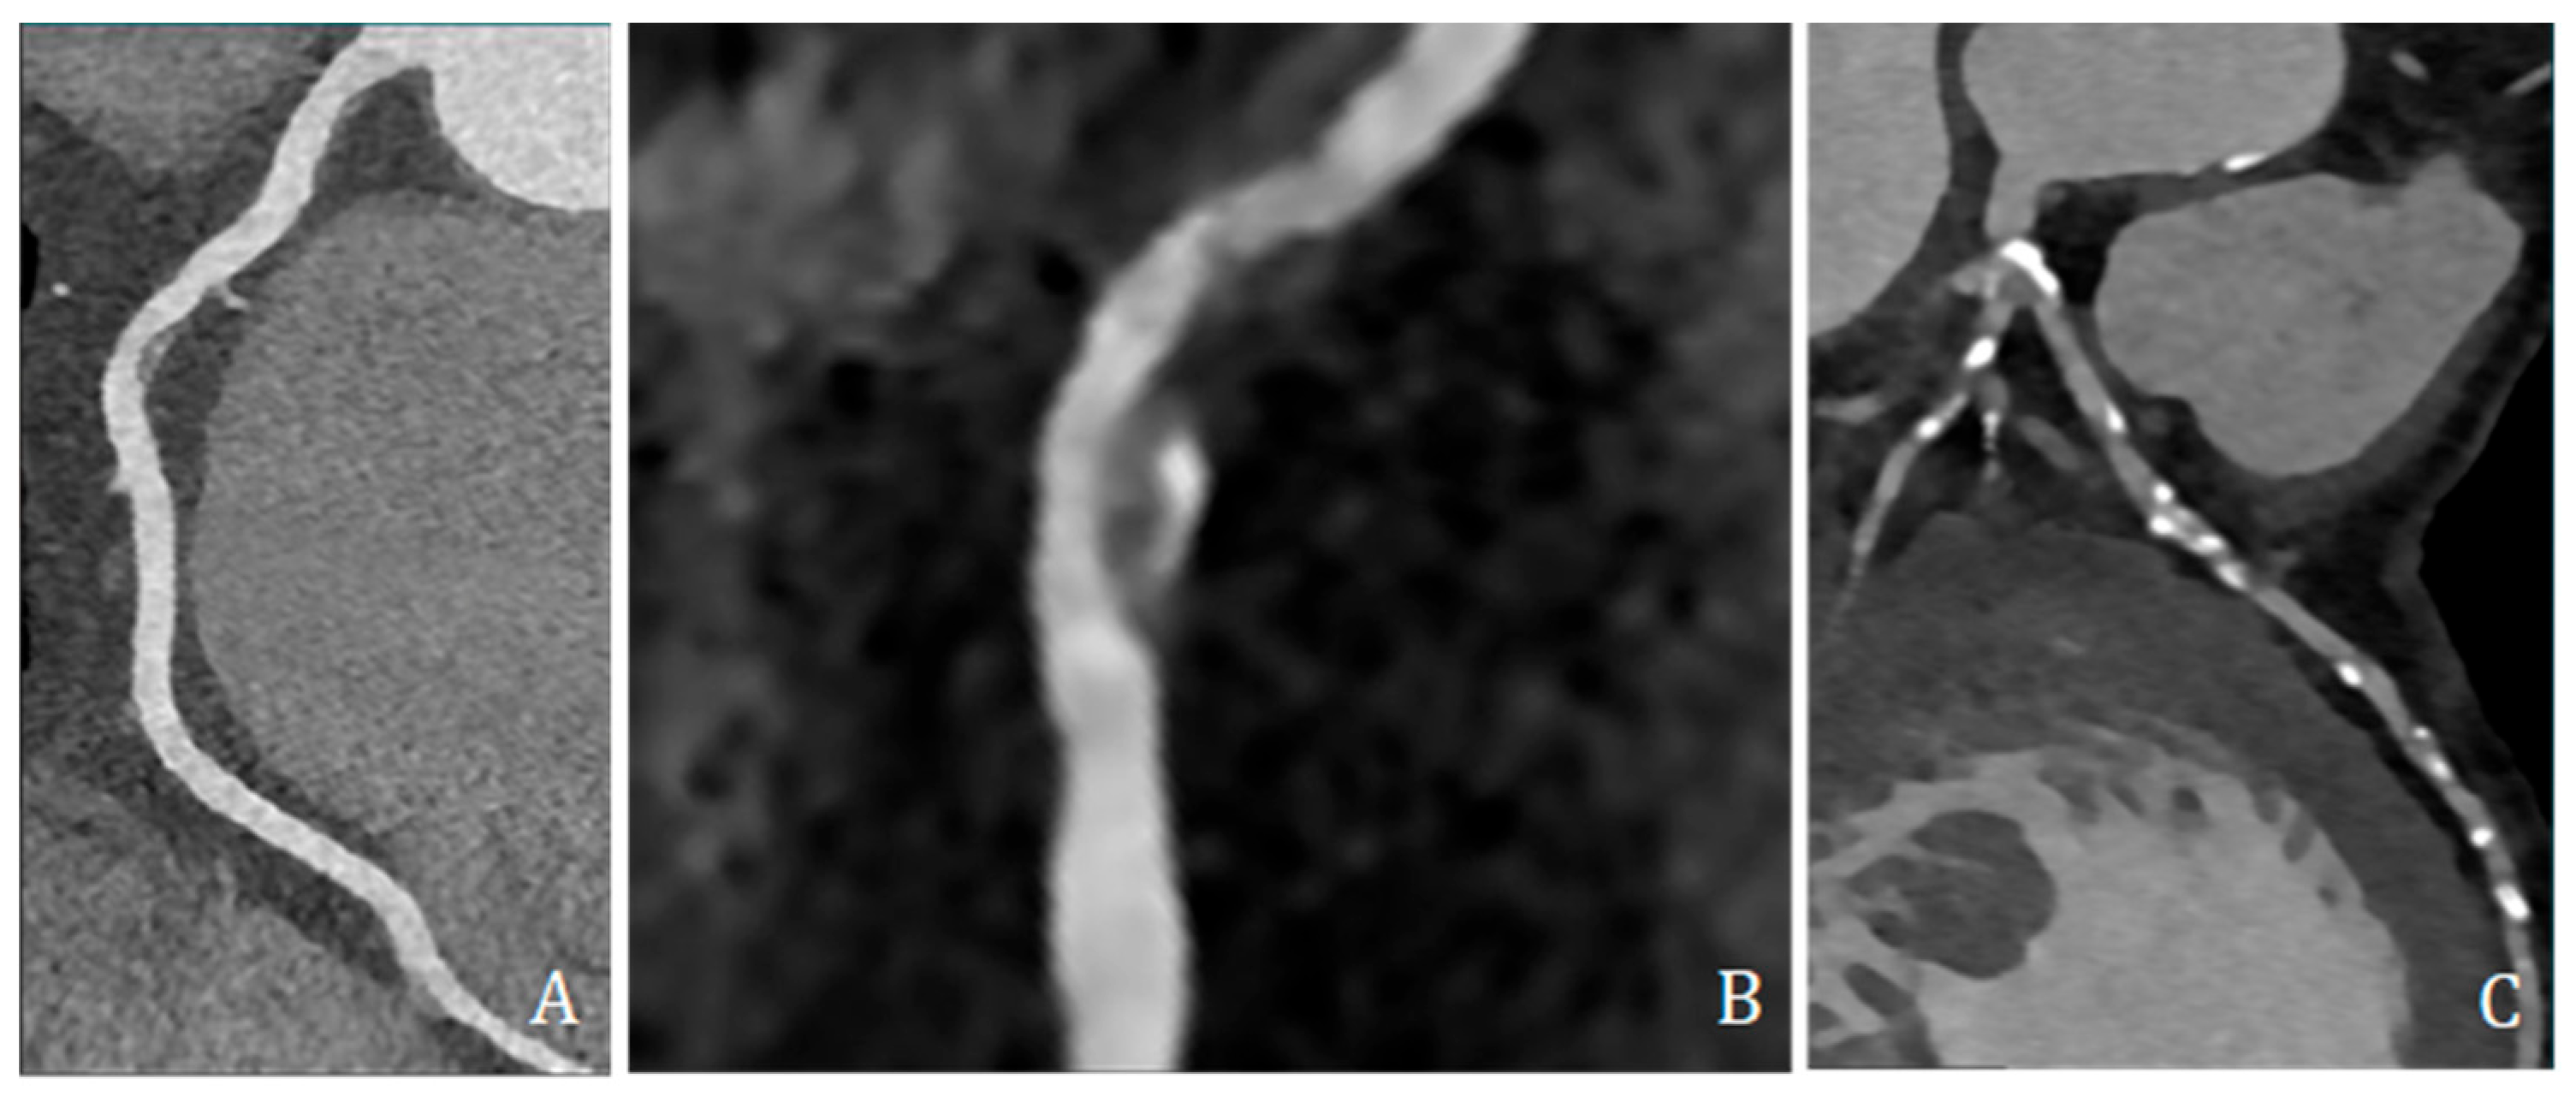

High-risk plaque features were assessed and included low-attenuation plaque (LAP, ≤30 HU), spotty calcification (SC, dense foci > 130 HU within non-calcified tissue and <3 mm), and positive remodeling (PR, remodeling index ≥ 1.1) (Figure 4).

Figure 4.

Coronary CT angiography showing different plaques and morphologies along different coronary arteries. (A,B) show predominantly non-calcified plaque, with low density, positive remodeling, and spotty calcification; (C) shows several predominantly calcified plaques all along coronary arteries, mainly the left anterior descending artery.